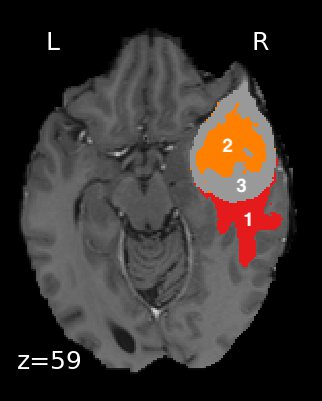

We used a multi-modal MRI brain tumor image segmentation benchmark dataset named BraTS. The MRI imaging sequences included in this dataset are T2-FLAIR, T1, T1Gd, and T2-weighted (Figure 1). The four modalities are concatenated as the fourth dimension (channel) on top of the X, Y, and Z dimensions. There are 750 patients (484 training and 266 testing) from BraTS’16 and ’17. The target of this dataset is to segment gliomas tumors and subregions. The tumor can also be partitioned as peritumoral edema, GD-enhancing tumor, and the necrotic (or non-enhancing) tumor core (Figure 2). The tumor can also be delineated as a whole tumor (WT), tumor core (TC), and enhancing tumor (ET) (Figure 2), which is the label definition we used in this work. Human expert annotation is conducted and provided within the dataset. This dataset is provided by Medical Segmentation Decathlon, and can be downloaded from the AWS Open Data Registry.

Figure 2. Labels are defined as: 1—peritumoral edema; 2—GD-enhancing tumor, 3—necrotic/non-enhancing tumor core. Whole tumor (WT) is defined as (1+2+3); tumor core (TC) is (2+3); enhancing tumor (ET) is 2 alone.